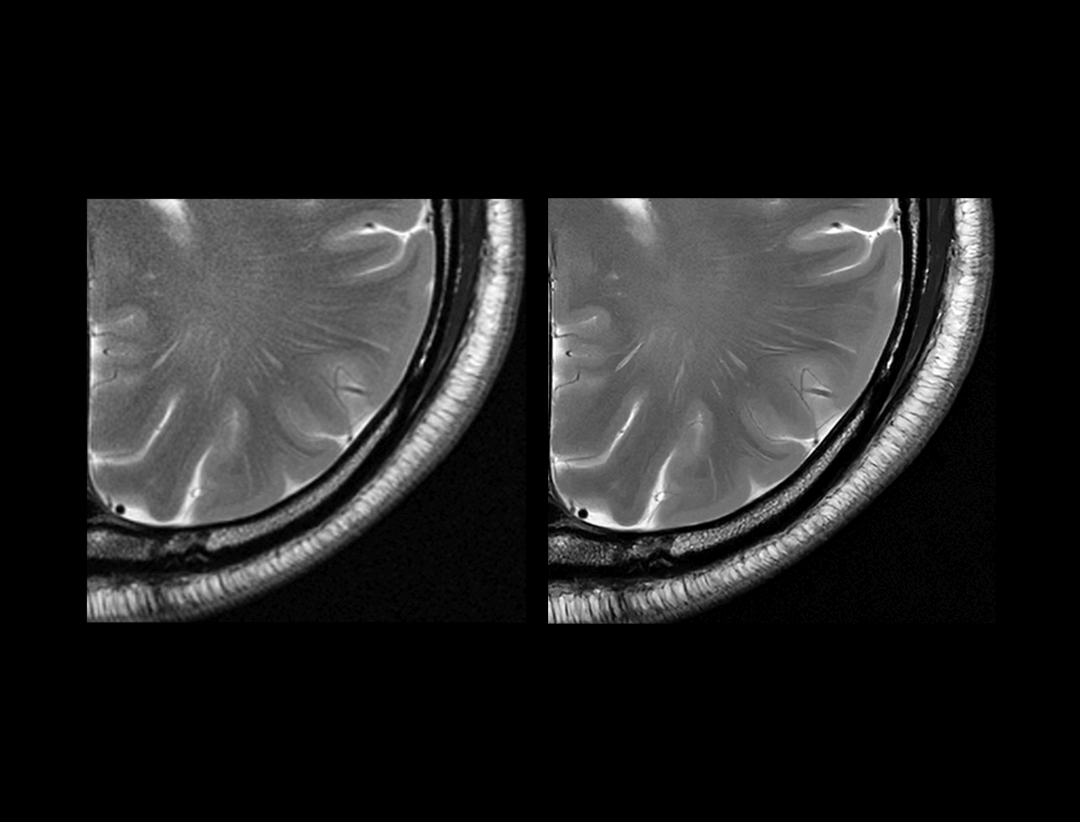

高分辨率

常规临床型1.5T (7:09 min) vs. uMR 660 (7:09 min)

0.21×0.20×4 mm3